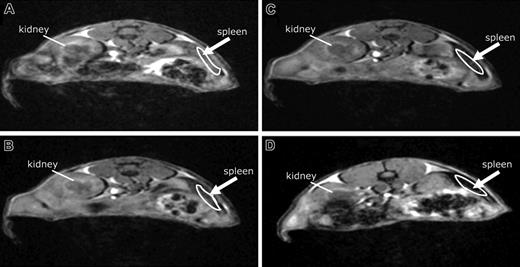

Confirmation of the SPECT data set was provided by T2* weighted MRI and histology using Feridex-labeled BMMs. MRI tests demonstrated increased hyperdensities of BMMs in spleen and liver compared with kidney from 0, 3, 6, and 24 hours (Figure 3A, B, C, and D, respectively). Histologic quantification of Prussian blue-stained cells (Feridex-labeled BMMs) showed the highest numbers of cells in spleen at days 1 and 7 (721 ± 98 and 625 ± 126, respectively) and was distributed primarily within the resident macrophage areas surrounding germinal centers. By day 7, a 5-fold increase of BMMs was found in spleen compared with liver (625 ± 126 vs 159 ± 37). Feridex-labeled cells were not detected in lymph nodes collected at day 1 after adoptive transfer of labeled BMMs via intravenous infusion. However, by day 7, BMMs were detected in both cervical and mesenteric lymph nodes (data not shown).

BMM tissue distribution assessed by MRI tests. MRI tests were used to track BMM migration. Feridex was administered to BMMs in vitro. After Feridex labeling, the BMMs were administered intravenously to immune-competent mice. Signal loss (darkened areas) is shown in the spleen (arrow) over time from 0, 3, 6, and 24 hours (A, B, C, and D, respectively) after adoptive transfer, demonstrating cell migration.